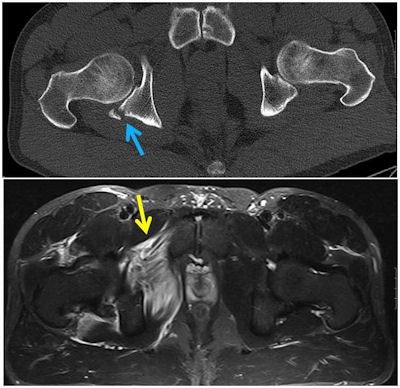

Radiography is the first-line tool in the evaluation of bony injury, while CT can add information and is important for detailed assessment of osseous injuries, noted lead researcher Dr. Daichi Hayashi, PhD, research assistant professor of radiology at Boston University School of Medicine, who was previously based at King's College London School of Medicine. Also, ultrasound is useful as an imaging modality for muscle injuries and detection of superficial foreign bodies. MRI is useful when detailed anatomical information is needed for evaluation of soft-tissue injuries, including muscles and joint structures.

"Radiography should initially be performed to diagnose or rule out acute osseous injury, such as fractures and dislocations," they pointed out. "Radiographically occult fractures may be detected using CT or MR imaging, if clinically suspected."

Muscle, tendon, and ligamentous injuries can be initially diagnosed using ultrasound, but for injuries of deep structures or large/extensive lesions, MRI can depict a larger region of interest, with more detailed anatomical information of the type and extent of lesion.